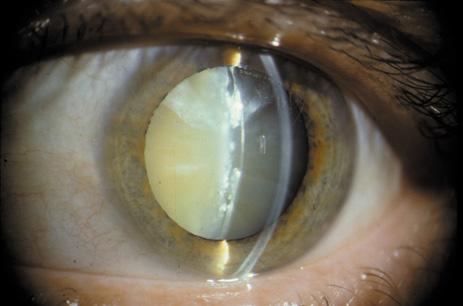

During the Middle Ages, Arabian physicians called the diffuse white appearance (Fig. 1) of total cataracts nuzul-el-ma, which means “a flowing down of water” or “blue water.” The Carthaginian monk Constantius Africanus, of the Monte Cassino Monastery, translated the ancient Arabic manuscripts into medieval Latin and applied the word cataracta, meaning “to rush down, as a waterfall.”2 In modern times, the development of devices that allow the lens to be examined at high magnification (e.g., the slit-lamp biomicroscope) has helped reveal many early changes that can occur in the human lens. Patients' increasing visual demands, as well as advances in the field of cataract surgery, have resulted in earlier removal of cataracts, and this has made the waterfall-like appearance of advanced cataracts a rarity.

Fig. 1. Bilateral mature cataract with white opacities visible to the naked eye. Cataract is the most common cause of treatable blindness in the world.